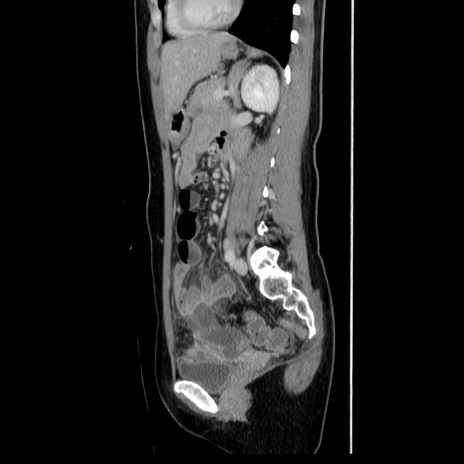

症例39(矢状断像)

【症例】40歳代女性

【主訴】上下腹部痛

【現病歴】2日目から下腹部痛あり。夜間は痛みで眠れなかった。昨日より上腹部痛と下痢が出現。臥位で痛みは軽快したため、休んでいた。本日になって臥位でも立位でも痛みが強くなってきたため救急要請。

【既往歴】子宮内膜症

【身体所見】部:平坦・軟、左上下腹部に圧痛あり、反跳痛あり。

【データ】WBC 21800、CRP 26.78

CT